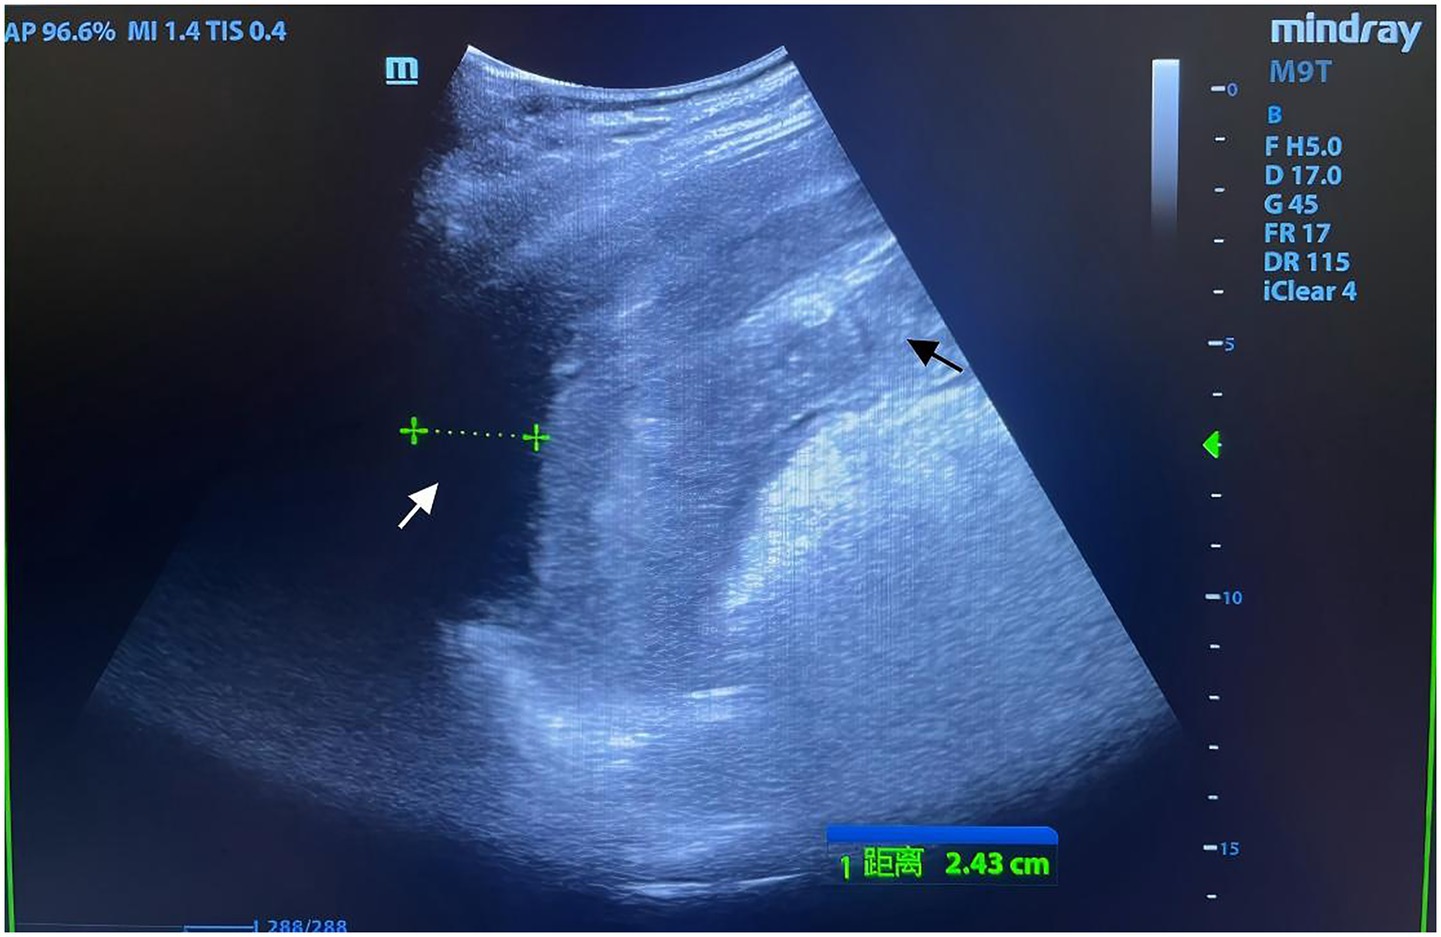

Physical examination revealed a 14-cm open wound on the left chest wall without thoracic cavity penetration and abdominal distension with dullness on percussion. During CPR, emergency trauma physicians performed a focused assessment with sonography in trauma (FAST), with the multidisciplinary team arriving promptly. FAST revealed significant intra-abdominal fluid and signs of splenic rupture (Figure 1), with no evidence of massive hemothorax or pericardial effusion in the thoracic cavity. Diagnostic abdominal paracentesis yielded non-clotting blood, strongly indicating traumatic splenic rupture with hemorrhagic shock as the primary cause of cardiac arrest. Due to profound hemodynamic instability, recurrent cardiac arrests, and inability to tolerate transport, emergency laparotomy was planned 10 min post-arrival and performed in the TRU. Within 12 min of ED arrival, tranexamic acid, albumin, and prothrombin complex concentrate were administered, and requests for packed red blood cells (PRBCs) and plasma were initiated. Central venous catheter (CVC) access was established. ROSC was achieved 13 min post-arrival; however, a second cardiac arrest occurred at 21 min. By 23 min, PRBC transfusion was initiated. ROSC was re-established prior to surgical incision. At 35 min post-arrival, an experienced trauma surgical team commenced emergency laparotomy in the TRU. Upon entering the abdominal cavity, approximately 2,500 mL of blood and 300 g of blood clots were aspirated. Severe splenic rupture was confirmed, with multiple longitudinal tears in the oblique dorsal capsule of the upper and middle splenic segments, the longest measuring 5 cm (Figure 2). Per the American Association for the Surgery of Trauma (AAST) criteria, the splenic rupture was classified as Grade IV. The splenic artery and vein were clamped for hemostasis, followed by splenectomy. Thoracic surgeons subsequently performed debridement and suturing of the chest wall wound and placed a chest drain.

Figure 1. Focused assessment with sonography for trauma (FAST) imaging during emergency resuscitation. Rapid-sequence FAST performed during urgent resuscitation revealed an indistinct splenic contour with irregular morphology and heterogeneous echotexture (black arrow). A hypoechoic perisplenic fluid collection, measuring 24 mm in width with poor acoustic transmission, was identified (white arrow). Intraoperative findings confirmed that the volume of intra-abdominal hemorrhage exceeded the extent visualized on FAST, correlating with the patient’s refractory hemorrhagic shock.